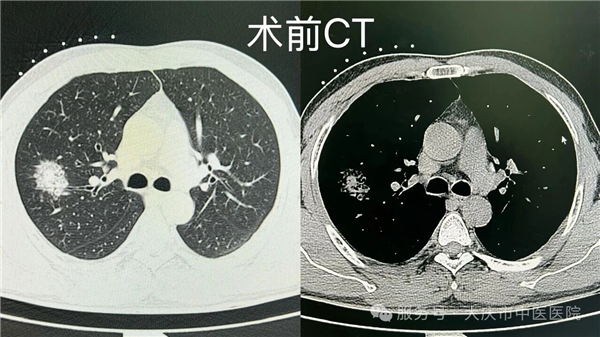

近日,在我院肺结节门诊牵头下,微创介入科联合 CT 室,成功开展一例肺结节同步病理活检与射频消融诊疗术。该技术在局部麻醉下,通过微创方式,同步完成病理活检取样与射频消融治疗,术中患者生命体征平稳,术后恢复良好。

传统肺结节诊疗通常分两步:先穿刺活检,等待3-5天病理报告,待病理结果回报后,再根据病情制定后续治疗方案,这不仅拉长住院周期,两次穿刺也增加了气胸、出血等风险。

本次开展的同步诊疗技术,在 CT 精准定位下,通过消融针到达病灶区域实施消融治疗,并通过同一通道获取组织标本进行病理检查,实现诊断与治疗环节的紧密衔接,有助于缩短诊疗周期,减少多次操作可能带来的相关风险。该技术的成功开展,是我院多学科协作及学科群建设的一次实践,为肺结节诊疗提供了新的技术选择。